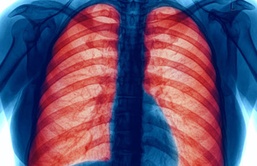

“Chronic obstructive pulmonary disease (COPD) is a term used to describe chronic lung diseases, including emphysema and chronic bronchitis, and is characterized by breathlessness. Some people with COPD also experience tiredness and chronic cough with or without mucus,” said Army Maj. (Dr.) Nikhil Huprikar, chief of Pulmonary and Critical Care Medicine Service at Walter Reed National Military Medical Center (WRNMMC).

“COPD makes breathing difficult for the 16 million Americans who have this disease. Millions more people suffer from COPD but have not been diagnosed and are not being treated. Although there is no cure for COPD, it can be treated,” according to the Centers for Disease Control and Prevention (CDC).